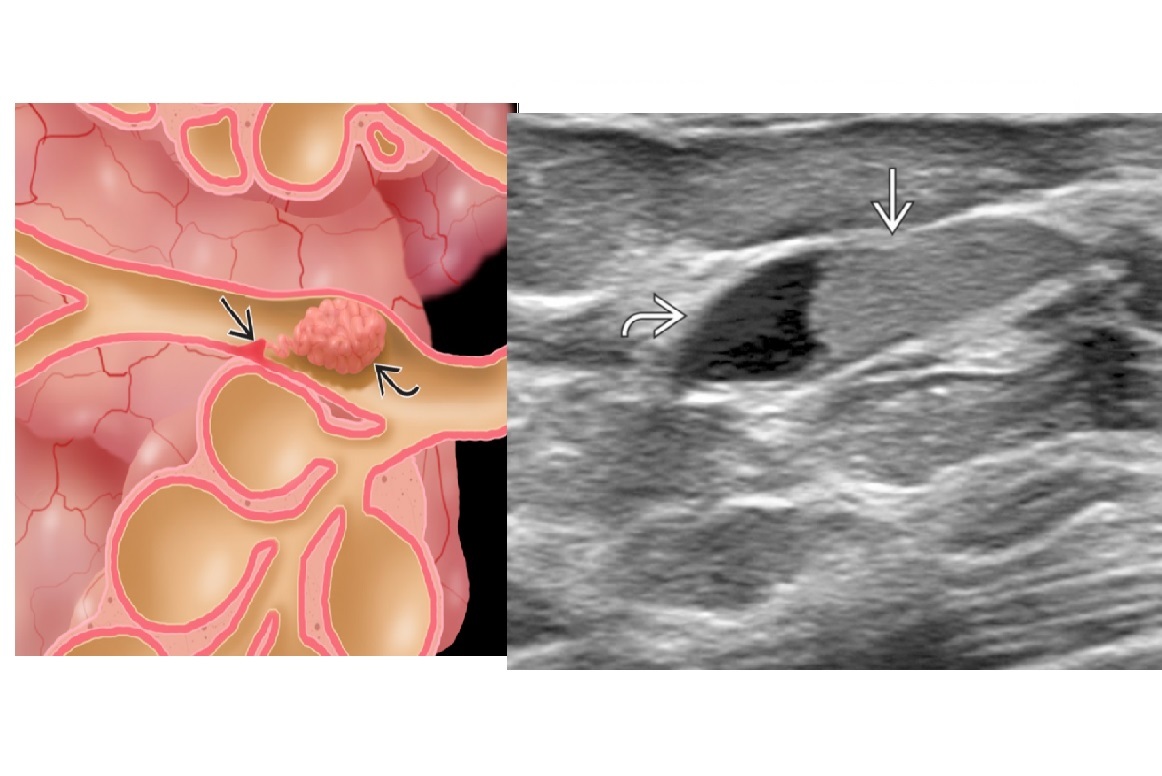

Intraductal mass or intracystic mass , Often mammographically occult, especially if central.Periareolar/retroareolar. Bloody or spontaneous clear nipple discharge

A

Papilloma